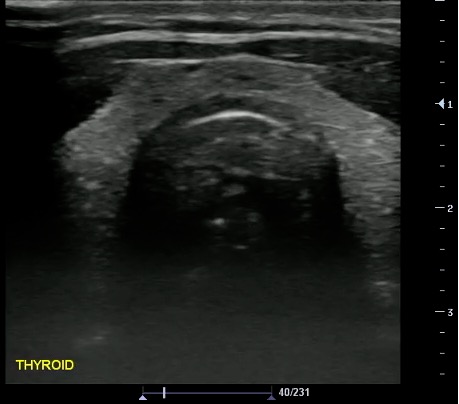

- Normal findings

- Homogeneous ground-glass appearance

- Hyperechoic relative to adjacent muscles

Video 21. Normal Thyroid - Measurements:

- Obtained in 3 dimensions (anteroposterior, transverse, and longitudinal)

- Nodule > 10 mm concerning for malignancy (controversial; not the only criteria)

- Additional measurements: Isthmus thickness (Transverse > 5mm abnormal), Lobe volume (Width x Length x Depth x 0.5)